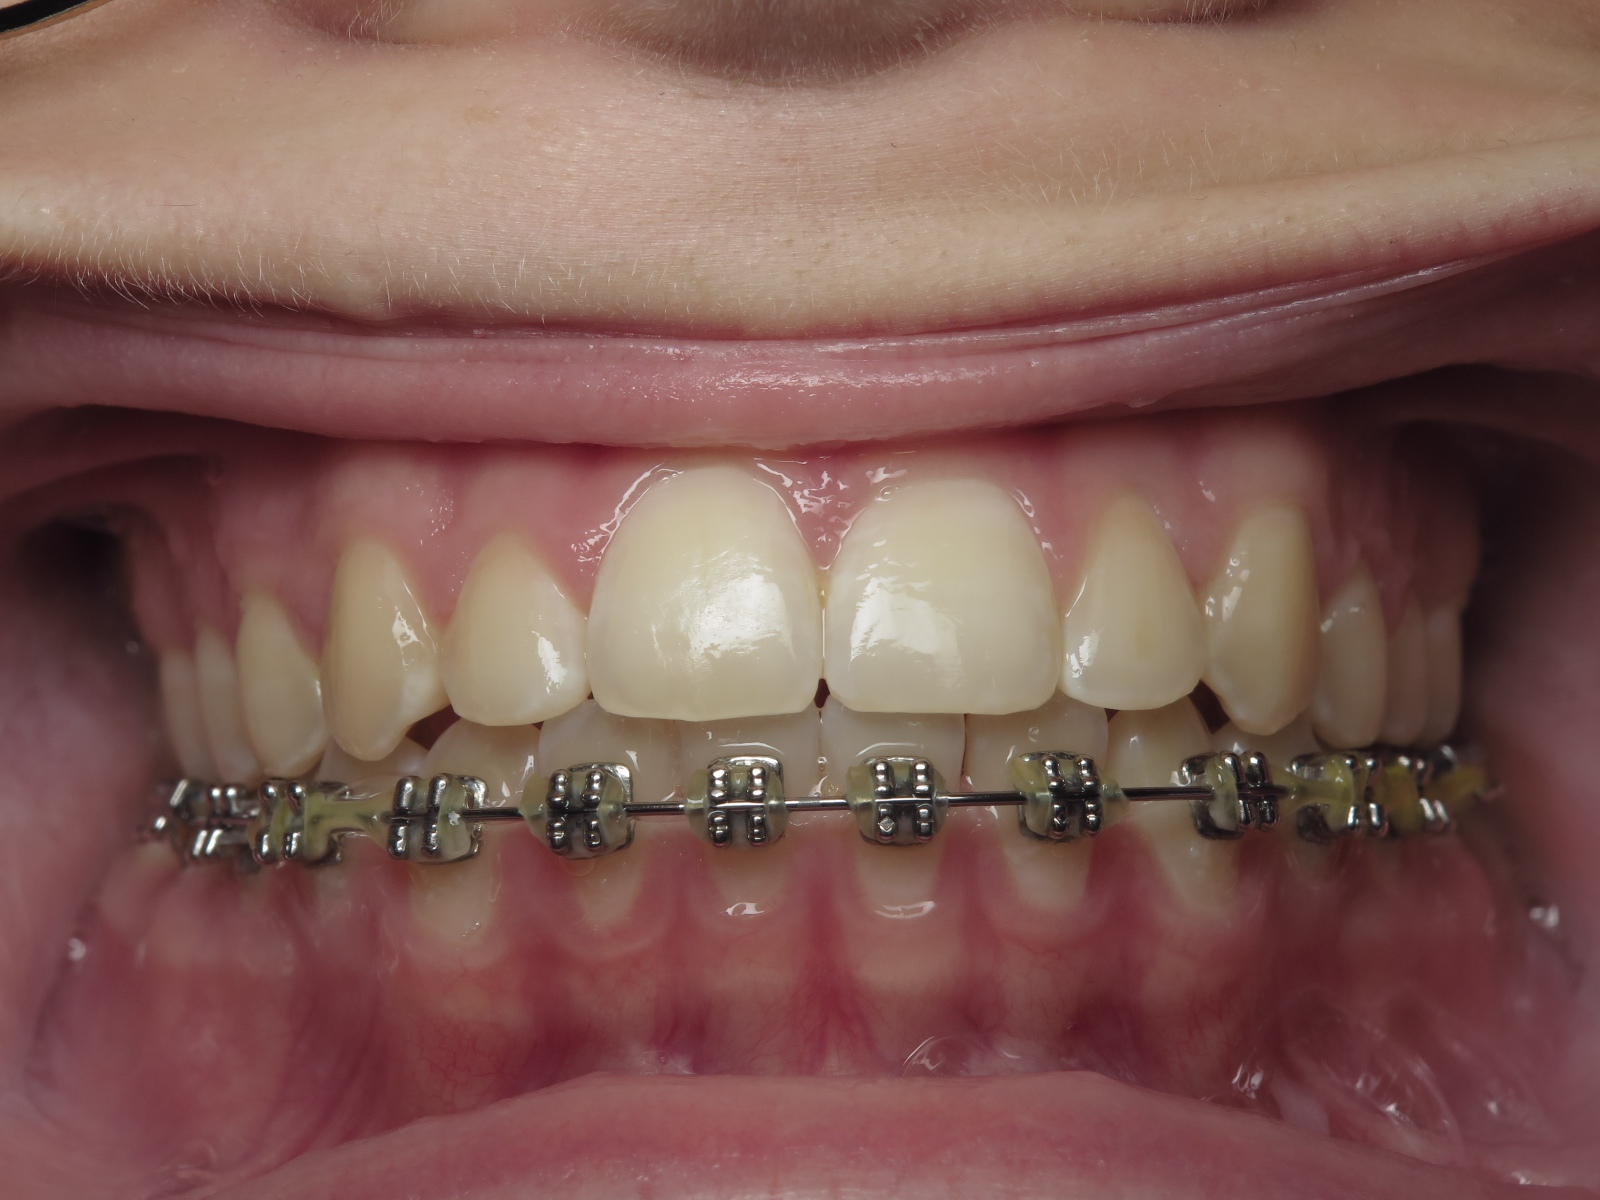

appareillage multibagues traitement en cours

bilan début et en cours de traitement